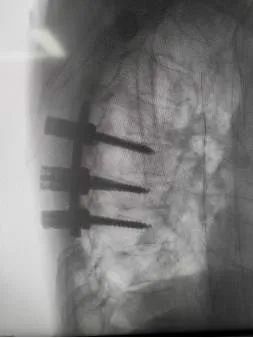

椎弓根螺钉置入

术后影像学照片